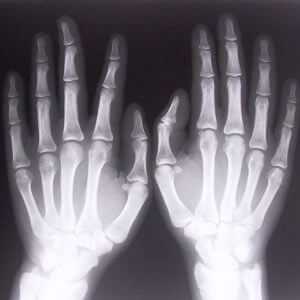

При болях, нарушении функции кисти или запястья только на одной руке для определения отклонений от нормы могут сделать рентген-фото лучезапястного сустава и кистей обеих рук.

Рентген кистей рук при ревматоидном артрите - важная диагностическая процедура, которая позволяет точно выявить стадию развития заболевания. Главными рентген-признаками данной патологии являются припухлости мягких тканей сустава. Также об артрите свидетельствует незначительное сужение межсуставной щели и визуализируемый остеопороз. На более поздних стадиях развития патологии будут видны эрозии костей, которые имеют вид некрупных краевых дефектов в суставных концах костей. В эпифизах костей фаланг пальцев могут виднеться округлые просветления.

Если повреждению подверглась только одна кисть, для более точного диагностирования патологии могут сделать рентген и здоровой конечности. Так будет легче провести сравнение и выявить отклонения.